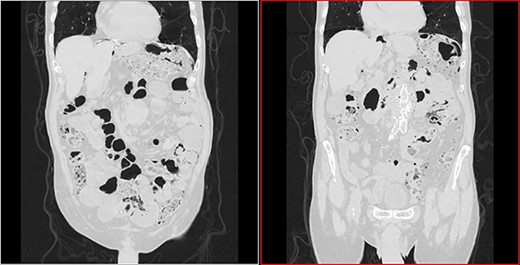

He arrived at the emergency department walking and with no clinical distress. He was complaining of hematuria for a month and worsening of chronic constipation in the last 2 days. Physical examination demonstrated discrete abdominal distention. Laboratory tests showed normal c-reactive protein (CRP), white blood cell count and lactate level. A new CT revealed no change in the previous findings: intestinal pneumatosis and pneumoperitoneum (Figs 2 and 3).

Coronal CT image in lung window showing pneumoperitoneum and ‘bubbles’ within the walls of small intestine and in the mesentery.